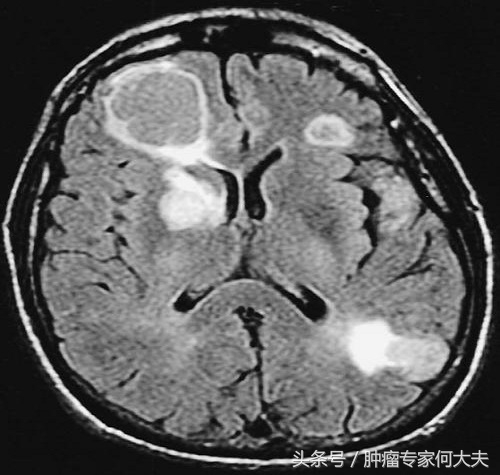

2016年4月老太太全身骨痛加重,并出现间歇性意识不清,并有晕厥现象,颅脑磁共振检查提示“多发脑转移”,在家属积极配合下,行全脑放疗10次,放疗后患者一度不吃不喝,消瘦明显,给予最佳支持疗法。患者体能逐渐恢复。治疗上改予“色瑞替尼”(国内暂没有,针对克唑替尼耐药后的替代品),尽管这药很贵,每月自费费用在五万左右,但家属对老人百般孝顺, 不离不弃,定期从外买药给老太太口服。服色瑞替尼的第一个月,老太太肠胃反应很大,反复恶心呕吐,严重腹泻,常出现严重低钾血症、低钙血症,后在中医中药的调解下逐渐耐受了,坚持口服该药1个多月后,老太太意识、精神状况明显好转,多项异常血液肿瘤标记物也明显下降。